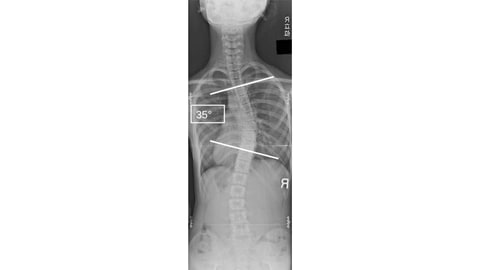

今回の研究による方法では、コブ角25°以上の中等症以上の側弯症を感度95.3%で検知できることが明らかになった。また将来的には、検査者なしに非侵襲的に自宅で繰り返し行なえる、セルフスクリーニングツールの開発につながることが期待される。